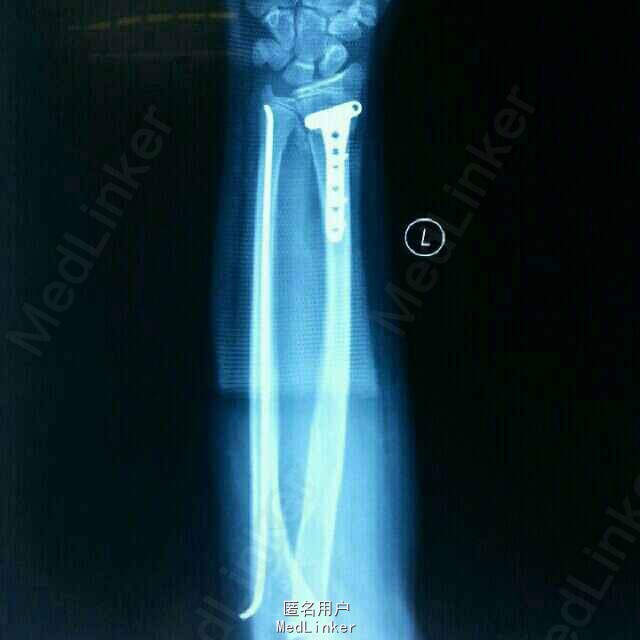

左前臂跌伤疼痛伴不能活动2小时入院。患者,男,13岁,2小时跑步时跌倒,左手撑地,感左前臂剧痛,不能活动,来院拍片示:左桡尺骨远端骨折。

检查:左前臂肿胀,触痛,活动功能障碍,手指未端感觉血运正常。拍片示:左桡尺骨远端骨折,重叠移位严重。

诊断:左桡尺骨远端骨折。治疗:伤后3天在全麻下行左桡尺骨骨折切口复位钢板弹性钉内固定术

讨论:1.青少年桡骨远端骨折与成人不同,青少年骨折发生在干骺端,很少波及关节面,且同时发生尺骨骨折,而成人多为波及关节面的粉碎性骨折。2.青少年桡骨远端骨折的治疗与成人基本相同,都是先行桡骨远端骨折钢板固定,尺骨用弹性钉撬拔复位